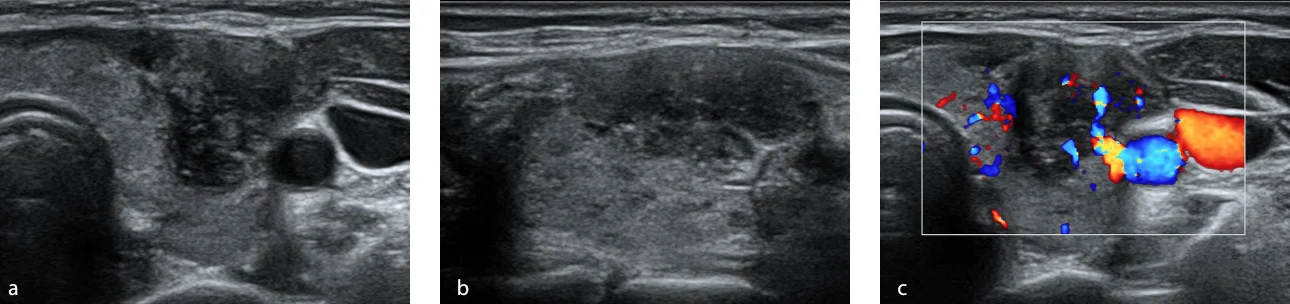

Fig. 1. US in grayscale axial section (a) and sagittal (b) shows a nodule in the middle third of the left thyroid lobe, solid, hypoechoic, wider than high, with apparent extrathyroid extension and pointed echogenic foci, measures approximately 1.3 x 1.3 x 2.1 cm, evaluated as ACR TI-RADS 5. At the application of color Doppler (c) shows internal vascularity.

During the diagnostic process, thyroid ultrasound was performed using the Mindray Resona I9 system. A solid, hypoechoic nodule was observed on the left side which was wider than high and had apparent extrathyroid extension and punctate echogenic foci. Additionally, internal vascularity was observed upon application of color Doppler. This nodule was evaluated as ACR TI-RADS 5 based on the findings (Fig. 1). Similarly, the Smart Thyroid AI of Resona i9 ultrasound system program was used to measure and analysy malignant signs and yielded comparable findings, except for the extrathyroidal extension which was assessed as having lobed/irregular borders. However, it also garnered an ACR TI-RADS 5 score (Fig. 2). The elastography examination indicated a heterogeneous appearance with an Emax stiffness of 40.53 kPa . Finally, the CEUS revealed that the lesion was heterogeneously iso-enhanced in comparison with thyroid parenchyma that showed early washout at 45 seconds (Fig. 3). The central portion of the nodule achieved peak intensity of 26.7 dB at 26.8 seconds, correspondingly; while the peripheral portion achieved peak intensity of 29.1 dB at 22.3 seconds (Fig. 4 ). The patient underwent Fine Needle Aspiration (FNA), which yielded a histopathological report of category VI of the Bethesda system, indicating papillary thyroid carcinoma. Additionally, confirmation of invasion in the prethyroid muscles was obtained during the surgical procedure.